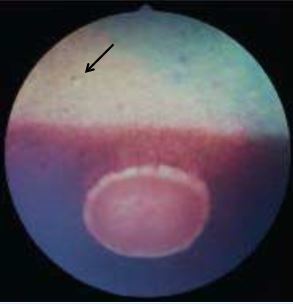

What clinical signs suggest the presence of a deep stomal abscess?

Fluorescein stain negative

Deep white corneal infiltrate

Corneal edema

Severe reflex uveitis

+/- vacularization